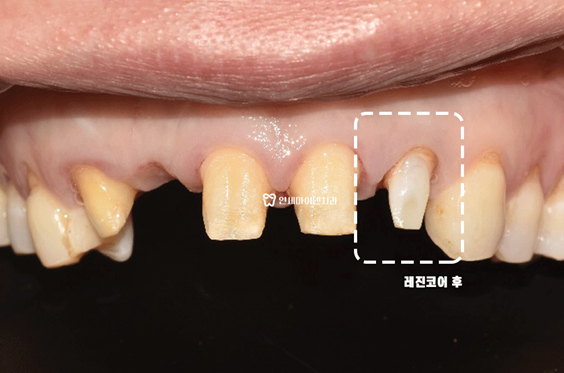

깨끗하게 내부 치료를 다시 하고 재감염이 없도록 레진코어까지 제대로 마무리했습니다.

앞니 재치료가 마무리 되었습니다.

보시는 것처럼 크라운도 예쁘게 마무리 되었습니다.

새로 한 크라운처럼 보이시나요?

원래 내 치아였던 것처럼 자연스러운 색상과 크기, 잇몸라인까지 잘 맞춰드렸습니다.

연세마이덴치과는 앞니 치료 시 <자연스럽게, 내 치아처럼, 대칭에 맞게> 를 가장 중요하게 생각합니다.

앞니신경치료 후 치아건강은 물론 심미성까지 모두 잡았습니다 ^^